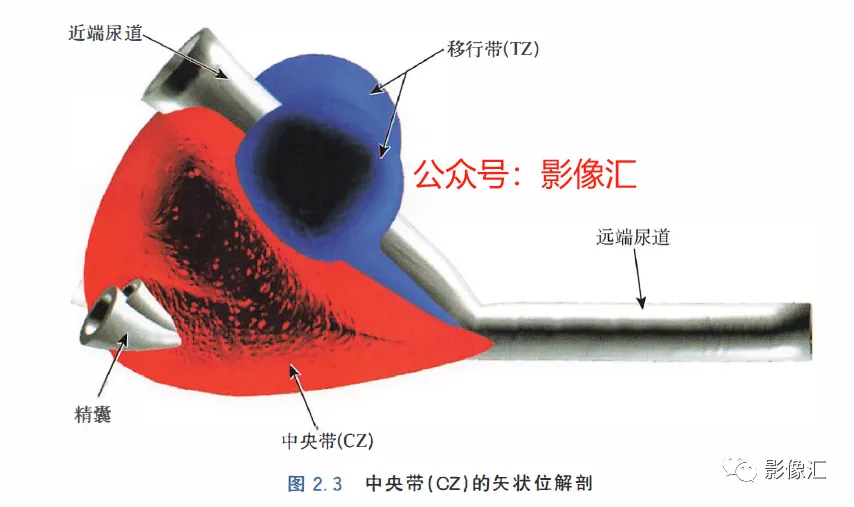

McNeal解剖模型认为前列腺根据周围不同结构环绕的关系而分为四个区域。尿道是描述整个前列腺区域解剖结构的解剖学标志。尿道由近端和远端尿道两个部分组成,每个部分约15mm长,由精阜分界。在精阜处,近端和远端尿道的走行呈35°。尿道壁由纵向走行的平滑肌纤维组成。围绕该内层的纵向肌肉层,是一层环形走行的肌层。两层平滑肌构成所谓的尿道内括约肌(IUS),其从膀胱颈延伸到尿道膜部的末端。IUS在膀胱颈的近端水平处最厚,随其向尿道膜部延伸,厚度逐渐减小。尿道膜部完整地被IUS环绕。在其前侧,前列腺内的lUS与前列腺肌性间质(AFMS)融合。两射精管走行方向与远端尿道平面平行,其开口于尿道腔内的前列腺小囊。移行带在前列腺组织中约占5%,构成两叶分别位于近端尿道两侧。其导管系统平行于尿道平面走行,止于精阜,射精管开口的近侧。移行带毗邻外周带,中央带和前列腺肌性间质,构成所谓的外科手术包膜,也就是说,确定了前列腺剜除术的外科手术平面。移行带和尿道周围腺体组织是良性前列腺增生(BPH)的发生部位。前列腺癌发生在移行带的比例为10%~20%。中央带在前列腺腺体组织中约占25%。其在前列腺底部形成金字塔形或锥形结构,在精阜水平处变窄至顶点。中央带的导管在射精管开口的两侧呈放射状走行。精囊和输精管穿入中央带形成射精管形似“精囊喙”。此区域由于缺乏前列腺包膜而成为解剖薄弱区。与射精管延续的中央带及伴行的筋膜和淋巴血管组织称为前列腺嵌入部(invaginated extraprostatic space,IES)。这是另一个解剖学上的薄弱区域,因此中央带疾病容易沿此区域播散。中央带相对发病率较低,发生在中央带的前列腺癌占5%~10%。外周带和中央带之间缺乏解剖学屏障,同时由于IES的存在,意味着前列腺尖部发生的肿瘤很容易进展到前列腺底部,并可早期造成前列腺周围间隙结构的受累。外周带约占前列腺腺体组织的70%。其包括前列腺表面的外侧、背侧和尖部,以多变的方式向腹侧延伸,与前纤维肌性间质相延续。前列腺不具有通常意义上的包膜结构,表面有一层腺样间质被称为“包膜"。前列腺“包膜”本身由纤维肌性间质构成,其在腺体周围形成一薄层结构。前列腺尖部没有这种间质层,造成一个解剖学上的蒲弱区域,称为梯形区域(trapezoidal area)。该区域腹侧以尿道膜部为界,背侧则以Denonvilliers和直肠筋膜为界,头侧以前列腺尖部(外周带)为界,尾侧则以直肠尿道肌为界。70%的前列腺癌发生在前列腺外周带。当前列腺癌起自前列腺尖部时,在早期即可通过梯形区域侵犯前列腺周围间隙。前列腺的背外侧神经血管蒂也是肿瘤易向外蔓延和侵袭的区域。AFMS约占前列腺体积的33%,是前列腺的非腺体区域,构成前列腺的前表面。在其最近端部分,其与逼尿肌和尿道内括约肌(IUS)的平滑肌纤维融合。头侧,其保持和尿道外括约肌(EUS)的关系;EUS的横纹肌纤维在该区域(前列腺尖部的前外侧)融合,构成前列腺外括约肌群。有四个“解剖薄弱“ 区域,通过这些区域,前列腺肿瘤可以生长并侵犯相邻的结构。这些区域是:精囊喙(图2. 6和图2. 17)

- 前列腺分为四个区域:移行带(TZ)、中央带(CZ) 、外周带(PZ) 和前列腺肌性间质带(AFMS)。